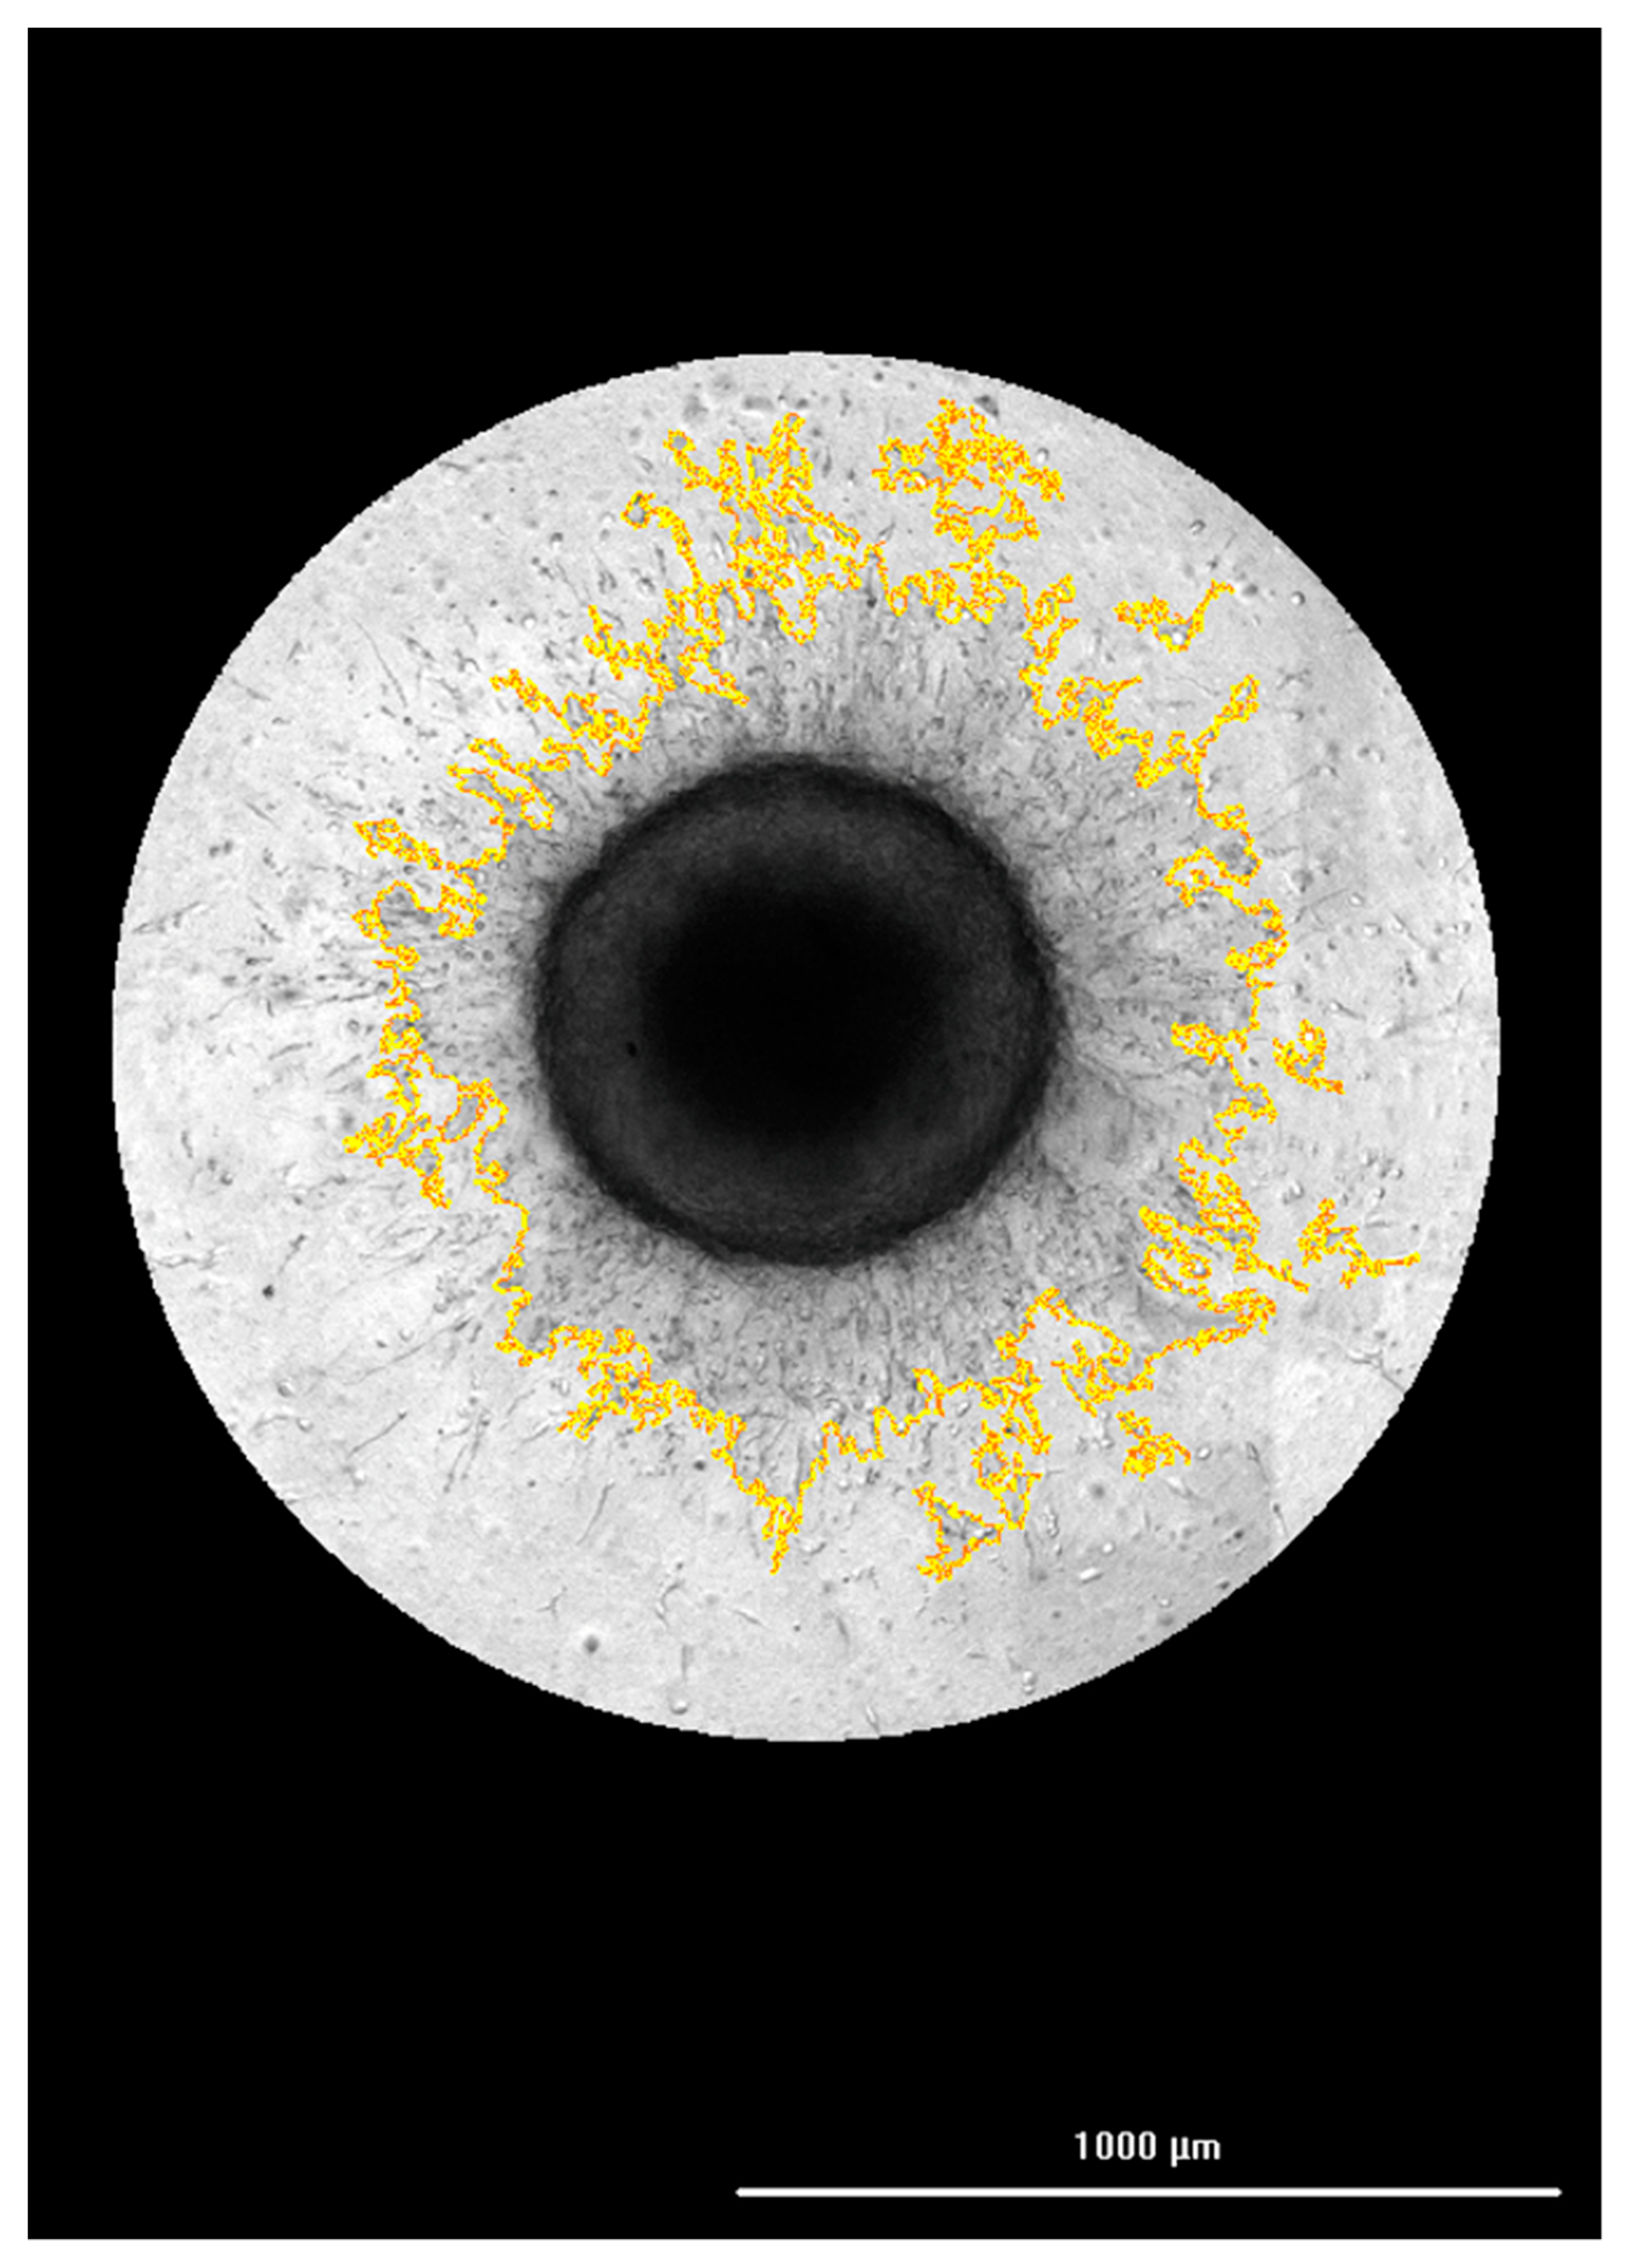

3.2. Correlation of FAM-fTHP-9 Signal with Increased Spheroid Invasion